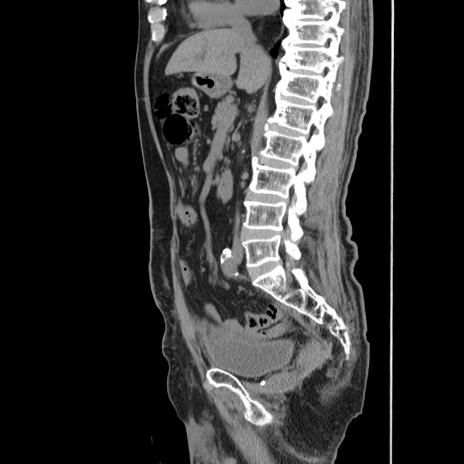

症例24(矢状断像)

【症例】80歳代男性

【主訴】左側腹部痛、嘔吐

【現病歴】本日早朝より左腹部に痛みあり。昼頃嘔吐認めたため、救急要請。

【既往歴】直腸癌(Mile手術)、胆摘

【身体所見】意識清明、BT 35.9℃、BP 221/93mmHg、SpO2 97%(RA) 、腹部:左ストーマ周囲に限局性の腹部膨隆あり。 膨隆部自発痛・圧痛あり・軟。

【データ】WBC 7700、CRP 0.09